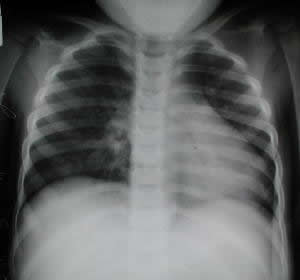

Radiología del Tórax

En la radiología preoperatoria posteroanterior PA, (abajo a la Izquierda), apreciamos el desplazamiento de la imagen cardiaca hacia la pared izquierda del tórax con franca luminiscencia de la región cardíaca correspondiente a la depresión esternal inferior, cuando la lateralización es acentuada, la rotación del eje cardiaco hacia la izquierda es evidente y el botón hilear derecho se proyecta de aspecto nodular y muy expuesto o bién, ausente retroexternal y esto frecuentemente es mal interpretado.

Rx. Tórax PA Rx. Tórax Lateral Izquierda